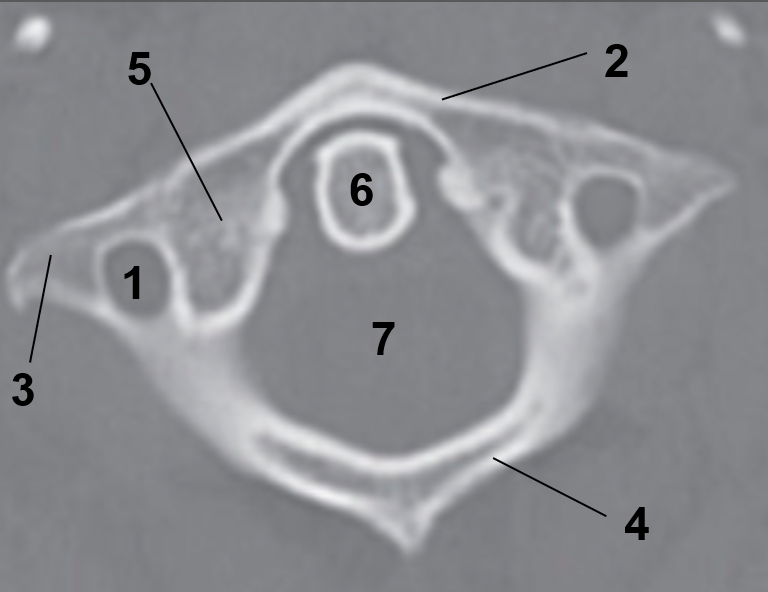

1?

Hard Palate

2?

Maxillary Bone

3?

Mandibular Rami

4?

Dens

5?

Transverse Foramen C1

6?

Spinal Cord

7?

Auricle

8?

Atlas